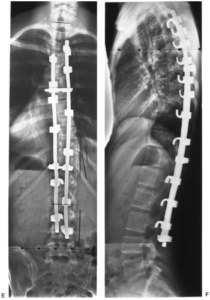

Стабилизационная система на рентгене.